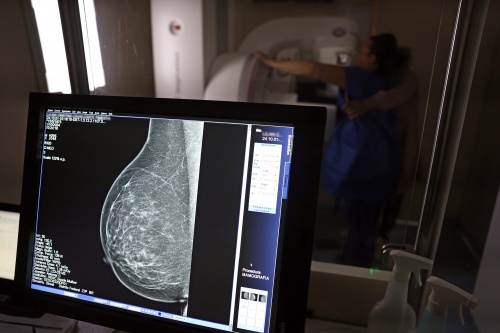

Falta de acesso a mamógrafos limita prevenção do câncer de mama

No mês de conscientização sobre o câncer de mama, um relatório destaca a importância de acesso igualitário ao rastreamento e tratamento da doença. Segundo o Atlas da Radiologia no Brasil, do Colégio Brasileiro de Radiologia e Diagnóstico por Imagem (CBR), o acesso aos mamógrafos ainda é um desafio.

O Brasil tem uma cobertura muito baixa de mamografias: 24%. O ideal recomendado pela Organização Mundial da Saúde é de 70%. Mesmo em lugares como o estado de São Paulo, que tem a maior concentração de mamógrafos do país, a taxa gira em torno de 26%.

Em setembro, o Ministério da Saúde ampliou as diretrizes de rastreamento, recomendando que mulheres entre 40 e 49 anos realizem mamografias, mesmo sem sintomas. De acordo com o Instituto Nacional do Câncer (Imca), mais de 73 mil mulheres recebem o diagnóstico de câncer de mama anualmente no Brasil.

“O que é efetivo na redução da mortalidade é você descobrir o tumor antes de ter sintoma clínico. Quanto menor o tumor, melhor para a gente descobrir o tratamento e maior a chance de cura. E a gente só consegue fazer isso com exames de imagem", diz Ivie.

Ela explica que no caso de diagnóstico de um câncer de mama com menos de 1 cm, a chance de cura é de 95% em cinco anos, independentemente se ele é do tipo mais agressivo. "E esses tumores só vão ser detectados na mamografia. Essas pessoas que têm que ir fazer mamografia são mulheres saudáveis. Não são mulheres doentes”, acrescenta.